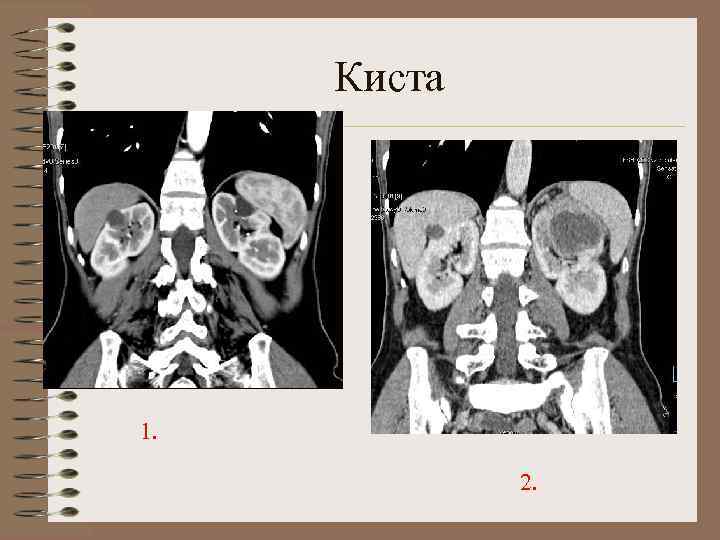

Рентгенологические признаки простой кисты почки • • • Увеличение размеров Деформация контура Симптом двойного контура Изменение расположения оси почки Смещение и сдавление лоханки Раздвигание больших чаш (симптом «разинутой пасти» ) Раздвигание и сдавление малых чаш Симптом перекреста малых чаш Расширение и уплощение малых чаш (симптом «серпа» ) Укорочение малых чаш ИССЛЕДОВАНИЕ МАЛОИНФОРМАТИВНО !

Обзорная рентгенограмма, ЭУ, томоурограмма - признаки ПКП

КТ- паренхиматозная фаза. Смещение и изменение расположения оси почки Симптом «клюва»

Классификация Bosniak (1986, 1997) 1. неосложненные доброкачественные кисты, не требуют наблюдения 2. минимально осложненные кисты , 2 F- динамический УЗконтроль -перегородки -отложения кальция в стенках и перегородках -инфицированные -гиперденсные, не накапливающие РКП

Классификация Bosniak 3. подозрительные, неопределенные. Показано оперативное лечение -нечеткий контур, утолщенные перегородки, обызвествления 4. озлокачествленные кисты. Солидный компонент, толстые перегородки, многокамерность (>3), накопление РКП( >15 HU)

Киста 1. 2.